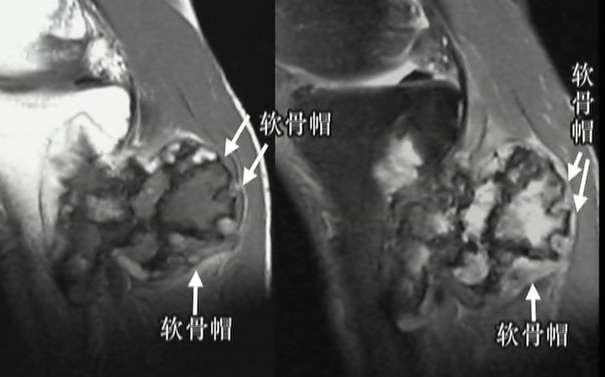

影像学表现:

X线表现:干骺端,背离关节生长;细蒂或宽基底与骨相连;顶部软骨帽钙化